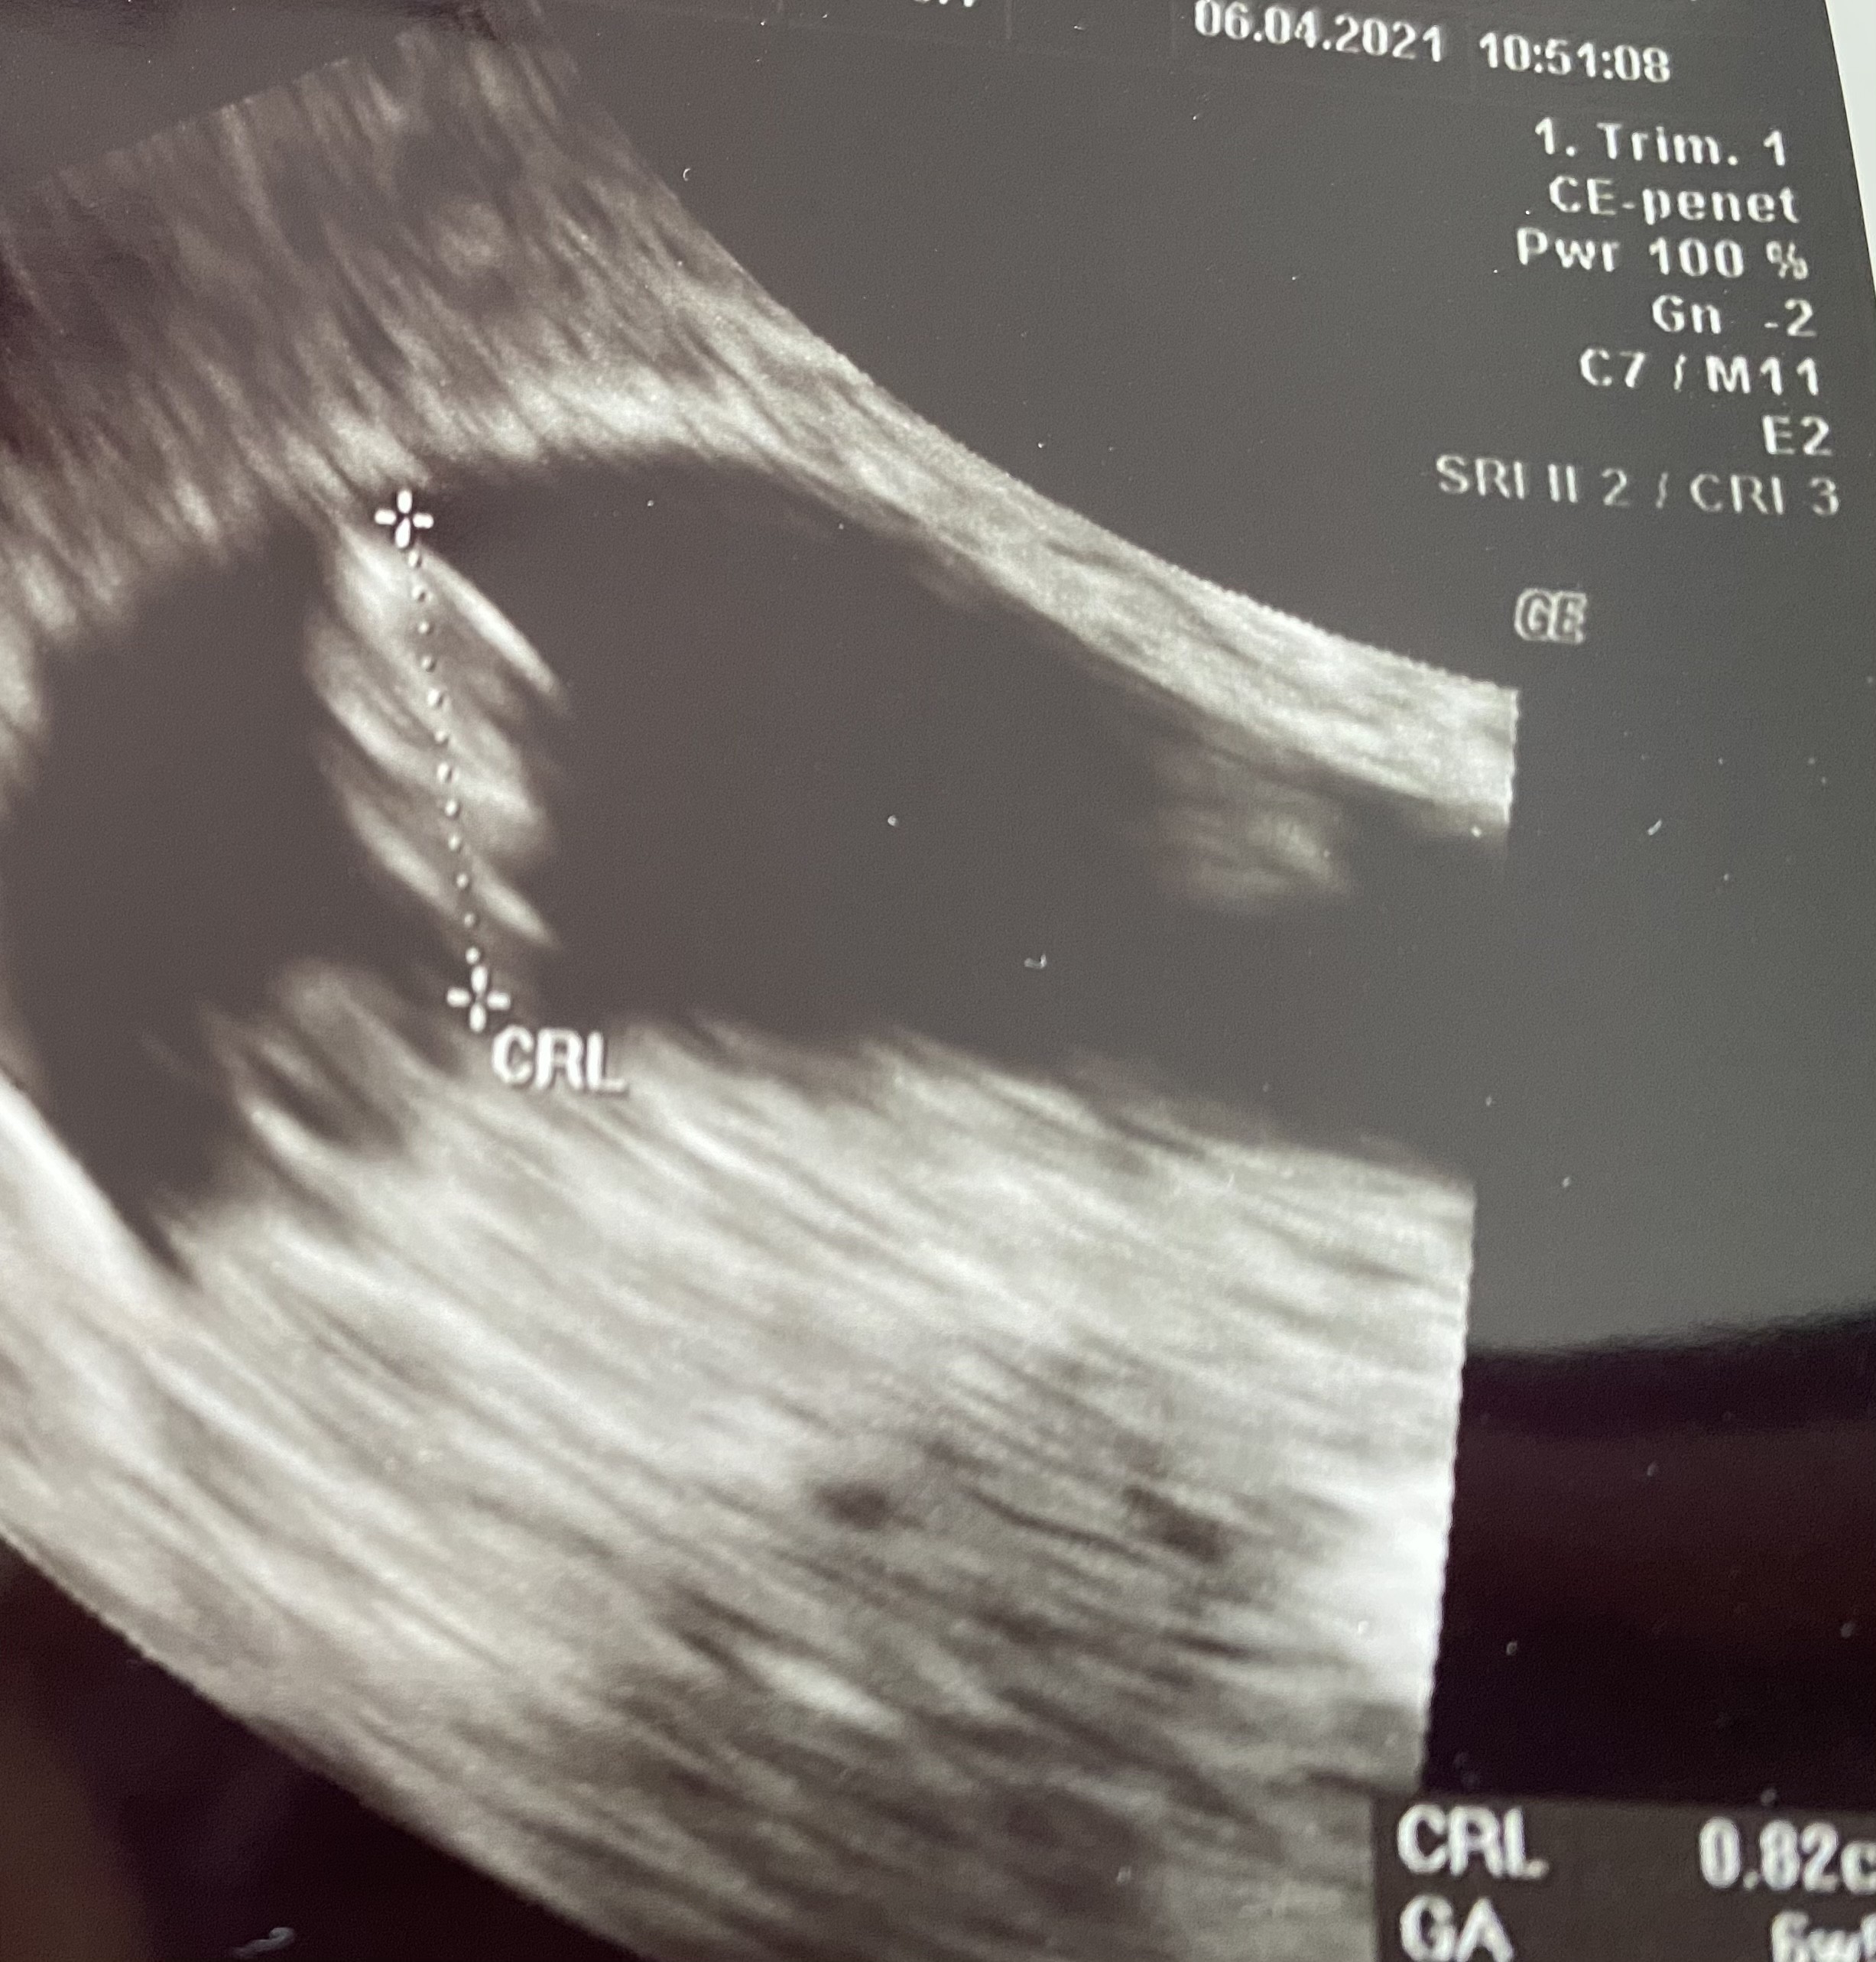

Hej Dziewczyny 🥰🥰

Ja już po wizycie , serduszko bije słyszałam 🥰 ma 8 mm wszystko ok, chodzę prywatnie i będę mieć od lekarza tez skierowanie na badania wiec będę mieć darmowe . Kolejna wizyta za 3 tygodnie . Jestem przeszczęśliwa 😃😃😃

Załączniki

• 90E2194E-57EC-4C37-894C-AB9B3451F390.jpeg

90E2194E-57EC-4C37-894C-AB9B3451F390.jpeg

1 MB · Wyświetleń: 104